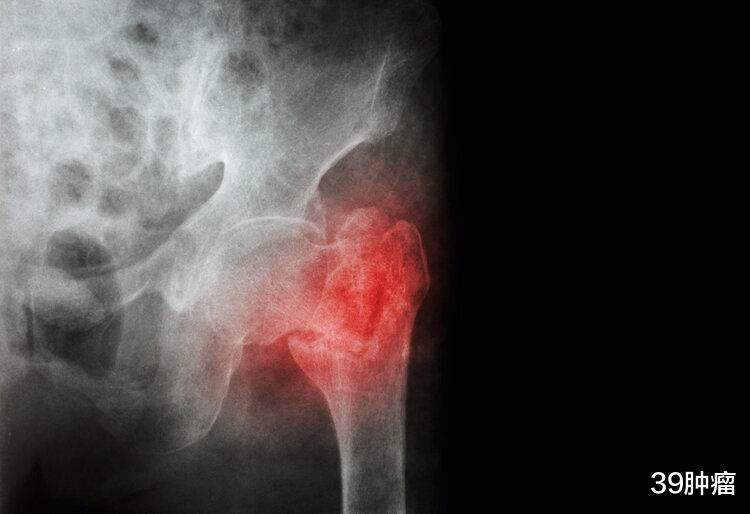

一般来说 , 老年人在跌倒时多是臀着地、屁股往后坐 , 这个姿势很容易导致髋部骨折 , 而髋部骨折素来有老年人“最后一次骨折”的称号 , 可见对健康威胁多大 。

数据显示 , 老年人发生髋部骨折的人群中 , 约有50%需要辅助才能步行、约25%需要长期护理 , 80%的髋部骨折老年人无法恢复到伤前的活动能力 。 发生髋部骨折后 , 一年内的死亡率可达到20~30% , 部分地区的死亡率更是达到了50% 。

其实 , 骨折本身不会致命 , 但老年人在发生骨折后需要长期卧床 , 很容易导致肌肉萎缩、下肢深静脉血栓、肺部感染等 , 这些并发症是要了老年人命的“真凶” 。